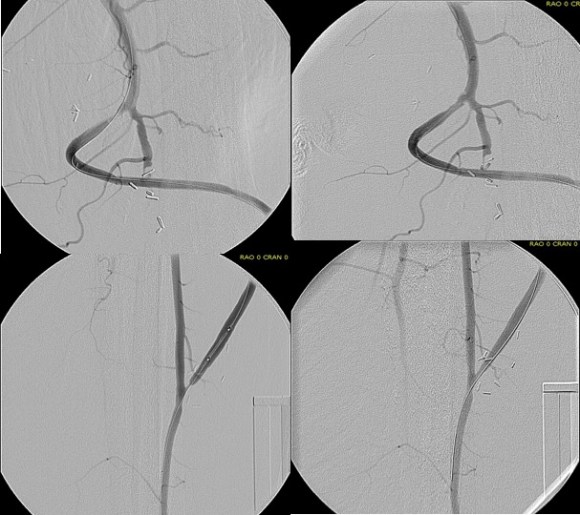

The bladder was dissected off the pubis to allow the graft to be tunneled to the right pelvis. A counter incision in the right lower quadrant abdomen and a mid thigh incision mobilizins the anterior compartment muscles to the posterior compartment allowed me to tunnel across the obturator foramen. The obdurator vessels need to be avoided or there will be bleeding. this mid thigh incision allowed exposure of the profunda femoral artery more proximally and allowe the graft to be tunneled anatomically to the below knee popliteal artery for anastomosis. A jump graft was taken off this graft on the thigh to the profunda femoral artery which was small and diseased -no more than 2mm in size. An axillary bypass to this profunda would be doomed to the compromised patency rate published for ax-fem bypasses giving them a bad name. The left superficial femoral artery was exposed and provided outflow to the left iliofemoral bypass which was tunneled far laterally under the inguinal ligament to avoid the scar tissue where the common femoral artery was.

There was immediately multiphasic signal in both feet on release of clamps. After closure of all the incisions and dressings, the right middle toe was amputated.

The patient recently came back for an 8 month followup. His grafts remained patent and he was walking without limitations. Given the high quality of the inflow (large iliac graft), and the amount of decent outflow -the right popliteal and profunda, the left superficial femoral and retrograde to the profunda, gives the patients some surety of longevity for his grafts. These grafts will need lifelong surveillance.